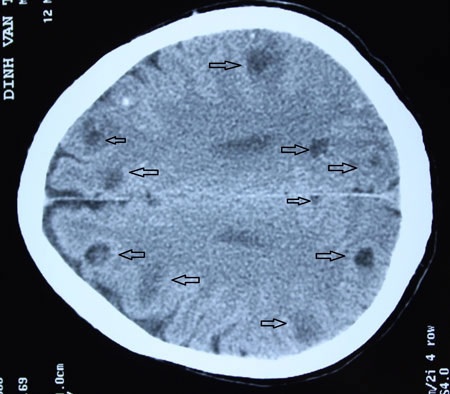

Các mũi tên chỉ các nang sán làm tổ trong não bệnh nhân 58 tuổi

Đúng như phỏng đoán, trên hình ảnh chụp CT, mỗi lát cắt chụp đã phát hiện 4 - 5 ổ sán não, tính chung trong não người bệnh lên đến trên dưới 50 ổ sán.

TS.BS Nguyễn Như Lâm, Trưởng khoa Vi rút - Kí sinh trùng, cho biết, phần lớn bệnh nhân nhiễm sán não đến bệnh viện khám với biểu hiện đau đầu kéo dài, thậm chí có co giật, điều trị tại tuyến cơ sở nhiều tháng, thậm chí nhiều năm không đỡ với chuẩn đoán đau đầu, động kinh, nhất là ở tuyến y tế cơ sở. Nhưng khi đi chụp cắt lớp, hình ảnh nang sán não dễ dàng được phát hiện, bởi nang sán có kích thước khá to, có những nang lớn từ 0,5-1cm.